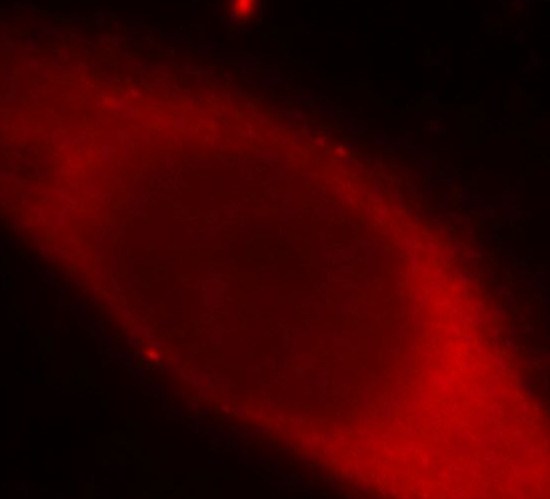

Immunofluorescent analysis of MCF-7 cells, using Galectin 3 antibody FNab03316 at 1:50 dilution and Rhodamine-labeled goat anti-mouse IgG (red). IP Result of anti-Galectin-3 (IP:FNab03316, 3ug; Detection:FNab03316 1:500) with MCF-7 cells lysate 1600ug.